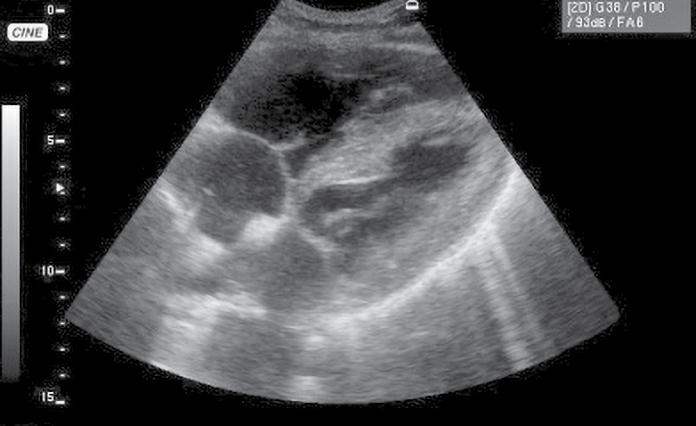

▶ Introducerea algoritmului de investigare a pacientului cu hipotensiune/ șoc RUSH (PUMP-TANK-PIPE) după cum urmează și luarea unor decizii bazate pe evidențe suport: o cordul („PUMP“)

• identificarea sacului pericardic, a colecțiilor pericardice și impactul de tip tamponadă (fig.1) cu risc de activitate electrică fără puls – necesitatea pericardiocentezei într-un serviciu de cardiologie-chirurgie cardiovasculară;

• contractilitatea globală a ventriculului stâng, identificând mărimea și statusul contractil – prezența unei insuficiențe cardiace acute (fig.2) cu necesitatea administrării medicației diuretice, inotrope, vasoactive în funcție de parametrii hemodinamici și corelarea cu aspectul plămânului și a venei cave; vizualizarea unui ventricul stâng hiperkinetic, cu reducerea volumui cavității (fig.3) ceea ce indică corelat cu aspectul VCI cu diametru redus (fig.4) o stare de hipovolemie ce necesită administrarea de fluide;

• aprecierea mărimii ventriculului stâng comparativ cu cel drept – identificarea unei supraîncărcări a ventriculului drept, cu suspiciunea de cord pulmonar acut (fig.5) și necesitatea de administrare de trombolitic pentru trombembolism pulmonar;

Fig.1. Secțiune subxifoidiană. Colecție pericardică. Cavități cardiace drepte colabate. Ventricul stâng cavitate redusă

Fig.2. Secțiune subxifoidiană. Cord dilatat. Perete ventricul stâng redus în dimensiuni

Fig.3. Secțiune subxifoidiană. Cord hiperkinetic (cavități reduse)

Fig.5. Secțiune subxifoidiană. Cord drept dilatat

Fig.6. Secțiune intercostală dreaptă. Colecție pleurală masivă. Atelectazie pulmonară de compresiune

Fig.7. Secțiune intercostal drept. Colecție Spațiul Morrison

Fig.8. Secțiune longitudinală suprapubiană Colecție recto-vezicală